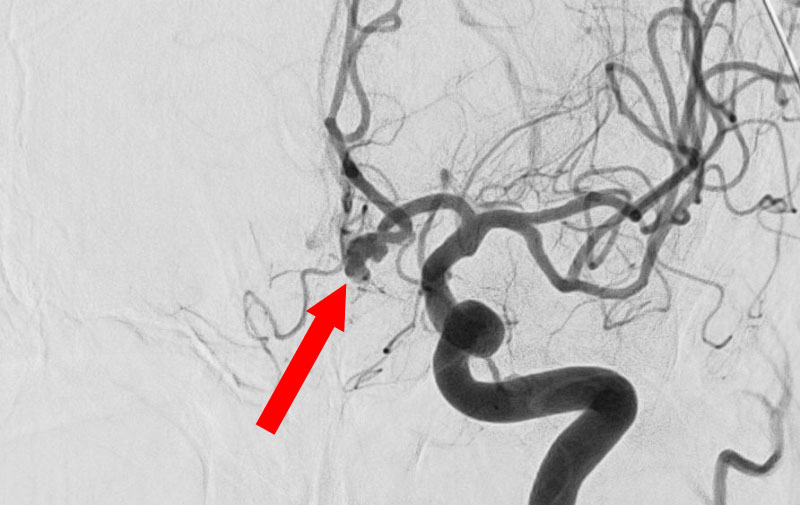

くも膜下出血

左中大脳動脈瘤破裂

40代

救急外来

No.1596 手術前